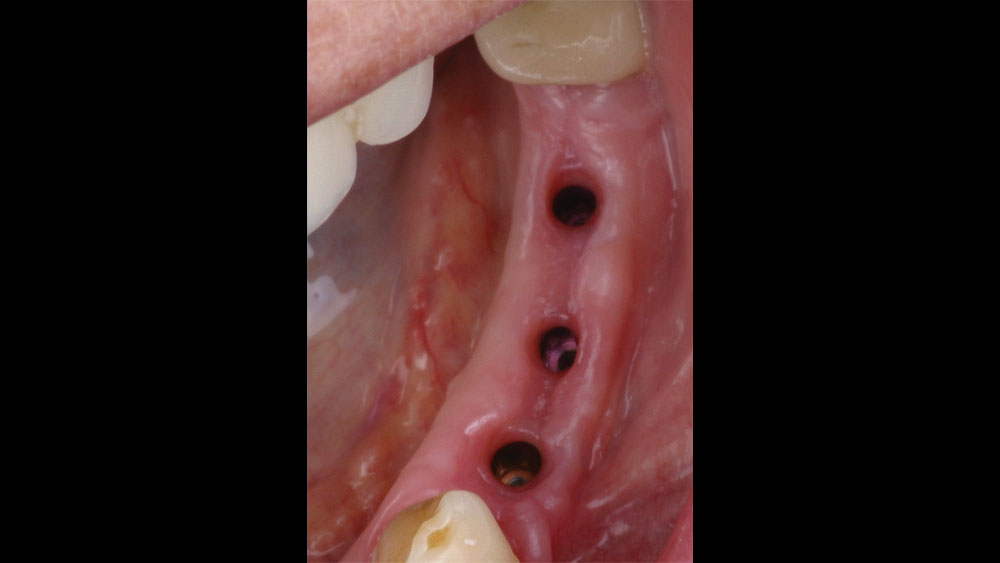

In this case, the patient presented with pain in the lower left posterior quadrant of her mouth. Upon examination, it was discovered that she had two failing premolars side by side, both of which had received cast restorations several years in the past. Failure was due to recurrent decay beneath those restorations. Her molar #19 had also been removed several years ago, resulting in a span where three adjacent teeth required replacement.

The patient selected implant treatment to replace her teeth. Screw-retained crowns were chosen instead of a cementable restoration, primarily due to the ease of retrievability afforded by screw retention. Because the posterior location of the restorations required resistance to occlusal forces as well as acceptable esthetics, I selected BruxZir® zirconia as the material; its high flexural strength and natural translucency fulfilled both requirements.

The question then became whether to use a splinted restoration in the form of a BruxZir screw-retained bridge, or unsplinted BruxZir screw-retained crowns. An assessment of this patient, as well as the pros and cons of both restoration types as previously outlined, led to the decision that an unsplinted restoration was the preferred treatment in this case. The key factors in this choice were as follows: